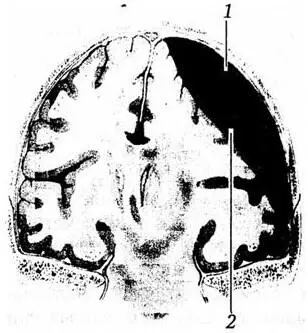

Субдуральные гематомы (рис. 9) морфологически характеризуются скоплением крови под твердой мозговой оболочкой. Как уже было сказано, в большинстве случаев они формируются по механизму противоудара и зачастую связаны с полюсно-базальными очагами ушиба головного мозга. Анатомия субдурального пространства предопределяет ббльшую площадь и объем данных гематом, чем эпидуральных. Основными источниками формирования субдуральных гематом являются поврежденные: корковые сосуды в зоне ушиба головного мозга; парасинусные вены и лакуны; венозные синусы. Для субдуральных гематом характерен большой диапазон вариаций их объема. Считается, что типичные клинические проявления синдрома сдавления головного мозга могут быть выражены только при объеме гематомы не менее 75 мл. Однако такие неблагоприятные факторы, как сопутствующий ушиб головного мозга, экзогенная интоксикация, повторная ЧМТ, способствующие увеличению объема мозга, могут вызывать развитие выраженной очаговой полушарной симптоматики и дислокационного синдрома при гематомах объемом 30 – 40 мл.

Рис. 9 . Схема субдуральной гематомы: 1 – dura mater; 2 – haematoma

Субдуральные гематомы задней черепной ямки объемом 30 – 50 мл считаются большими, так как приводят к раннему блоку ликворопроводящих путей на этом уровне и аксиальной дислокации мозжечка в затылочно-шейную дуральную воронку.